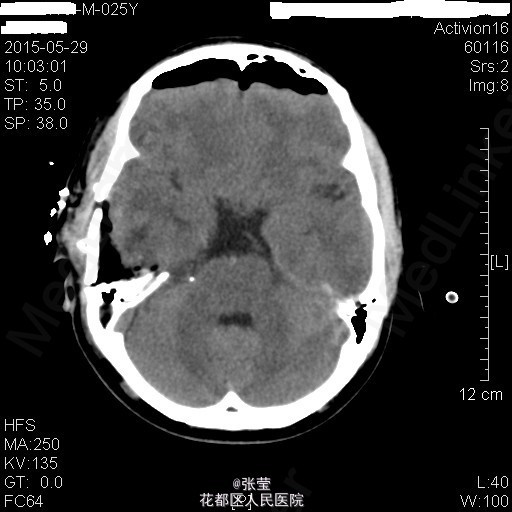

青年男性,主诉:头晕伴肢体乏力1周。 现病史:患者1周前始无明显诱因反复出现头晕,伴左侧肢体乏力、行走不稳,偶伴头痛、恶心感,休息后可稍缓解,无呕吐,无天旋地转感,无晕厥,无伴听力、记忆力减退等,发作无明显规律。至当地医院就诊,头部MR结果示:右间脑下方-脑干-桥前池-左鞍底区肿瘤,并瘤内卒中。

查体:神清,对答切题,双瞳等大等圆,直径约3mm,对光反射灵敏,双侧听力粗测正常,四肢肌力Ⅴ级。生理反射存在,病理征未引出。 辅查:颅脑MR:1、斜坡区占位,侵及中脑、脑桥右份及蝶窦,病灶ADC值增高,FA值下降,考虑脊索瘤并囊变、出血可能大。 2、MRA示双侧颈内动脉向外侧移位,余脑动脉未见明确异常。

患者入院后完善相关检查,排除手术禁忌症,于2015年4月7日行"神经内镜下经鼻蝶入路斜坡脑干占位病变切除+鞍底重建+左下腹脂肪取出术",手术顺利。 术后病理示:脊索瘤。 予抗感染、护胃、化痰、维持水电解质平衡及加强营养支持治疗,患者病情较前明显好转。